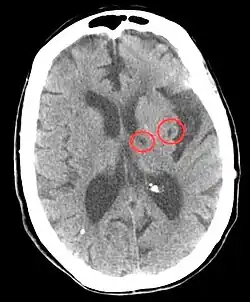

CT scan of two lacunar infarctions. Moments after an ischemic stroke, lesions are established that can be detected.

Hypertension is the leading cause of strokes and studies show that it increases the risk of a stroke by 220%[17][18] and stroke is the leading cause of long-term disability.[19] High blood pressure weakens arteries (small vessel disease) and causes blood vessels to be more likely to clog and/or burst. A lacunar infarction occurs when an artery is blocked and an intracerebral hemorrhage occurs when the blood vessels burst. In turn, the brain is more vulnerable to ischemic insults as there is a dysregulation in the supply of blood and oxygen.[19] More specifically, hypertension inflicts damage to small resistance arteries, which supply nutrients to the internal capsule, brainstem, thalamus, cerebellum, and basal ganglia, and cause cell death and tissue degeneration.[3] Blood clots also accelerate arterioscelerosis, which causes arteries to thicken and harden.[20] Essentially, hypertension is the biggest risk factor for stroke and tissue damage caused by a stroke is a major risk factor for cognitive decline, therefore the risk of stroke may act as a mediator in the relationship between blood pressure and cognition.[21] Besides lifestyle modifications, blood pressure control is the #1 treatment for stroke prevention. Antihypertensive medication show a protective effect against stroke-related cognitive impairments.[3]